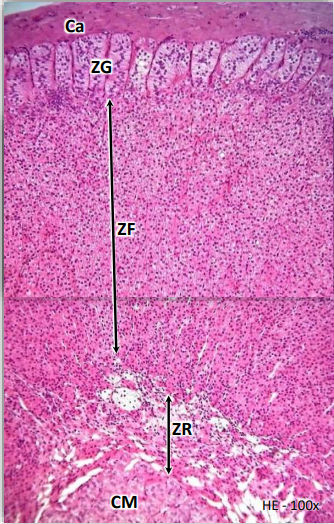

Região Medular e Cortical do Ovário

No ovário identificamos duas

porções distintas: a medula do ovário, que é constituída por tecido conjuntivo

frouxo, rico em vasos sangüíneos, célula hilares (intersticiais), e a córtex do

ovário, rica em folículos ovarianos, corpo lúteo e células intersticiais. Na

região cortical predominam os folículos ovarianos, os quais são formados por

ovócitos envolvidos por células epiteliais (células foliculares ou da

granulosa). A superfície do ovário é revestida por um epitélio (de origem

celomática) que varia do tipo pavimentoso ao cilíndrico simples (denominado

impropriamente de epitélio germinativo).

Logo abaixo deste epitélio

há uma camada de tecido conjuntivo denso, a túnica albugínea. O estroma do

ovário, entre as estruturas medulares e corticais, possui algumas células

fusiformes, denominadas de células intersticiais ou de Leydig. Estas últimas

respondem aos estímulos das gonadotrofinas e produzem hormônios sexuais,

principalmente androgênios. Na região cortical, dependendo da fase e da idade,

podem-se identificar: foliculos ovarianos, corpo lúteo e corpos albicantes.